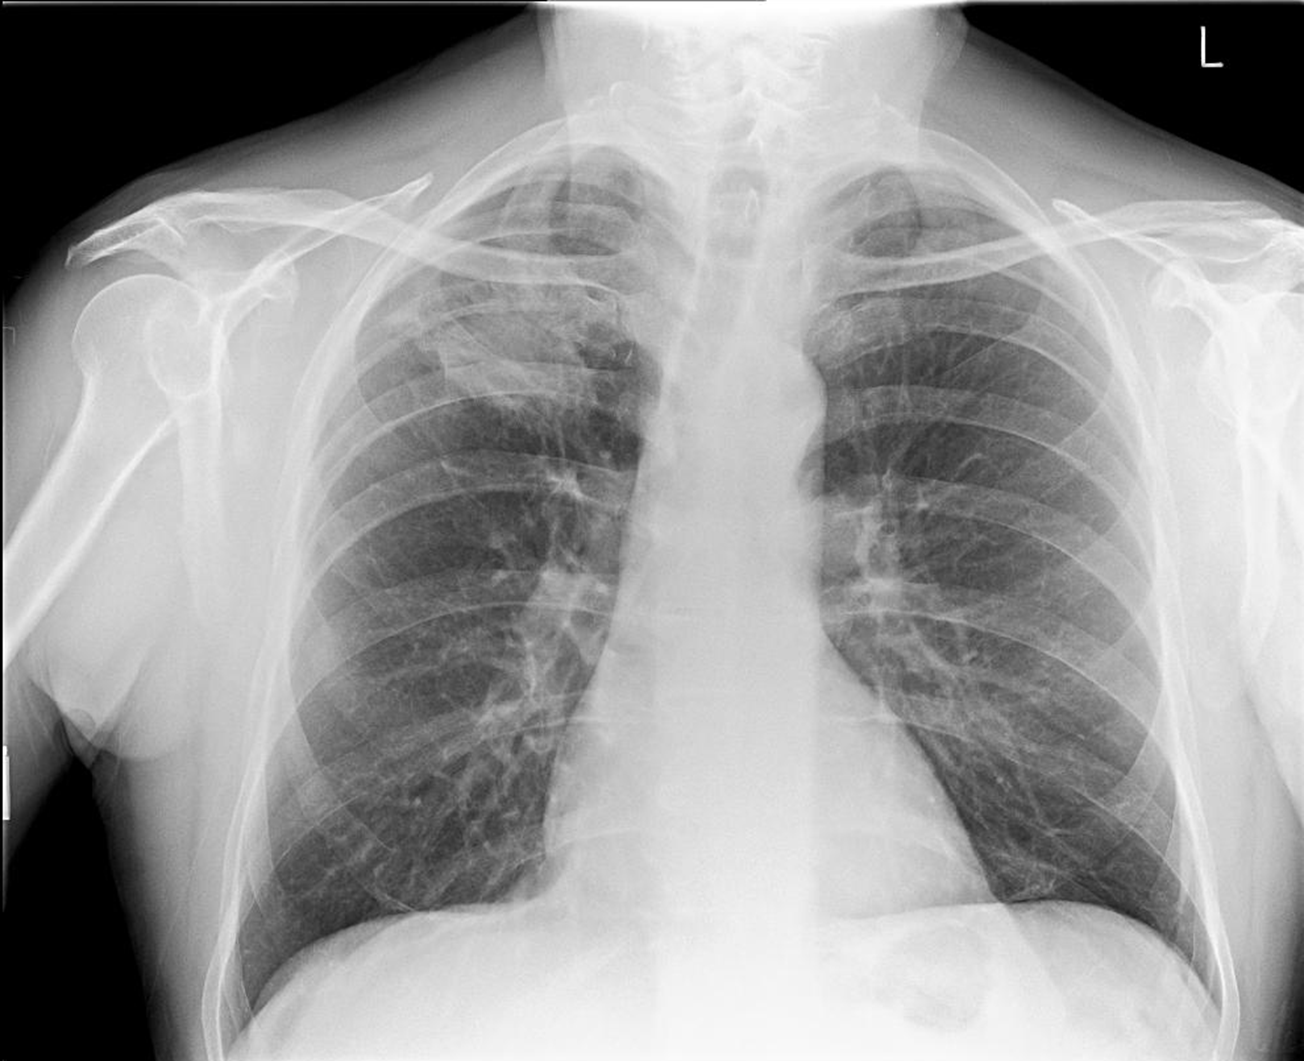

Classic TB radiograph

White in upper lobe and cavities

Reactivation

TB reactivation is more common in ____ ____ lobe

Right upper